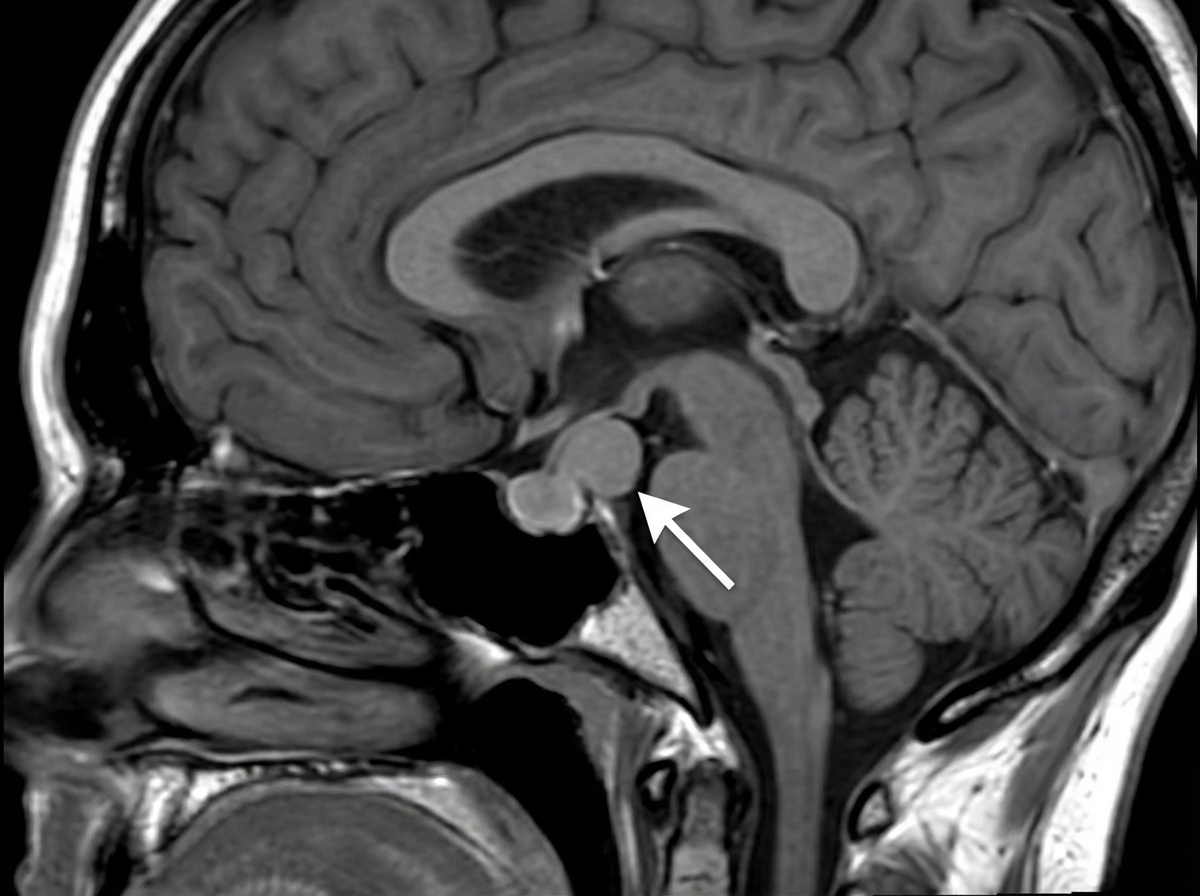

A 17-year-old teenager presents to the clinic with her parents complaining of headaches and loss of vision which began insidiously 3 months ago. She describes her headaches as throbbing, mostly on her forehead, and severe enough to affect her daily activities. She has not experienced menarche. Past medical history is noncontributory. She takes no medication. Both of her parents are alive and well. Today, her blood pressure is 110/70 mm Hg, the heart rate is 90/min, the respiratory rate is 17/min, and the temperature is 37.0°C (98.6°F). Breasts and pubic hair development are in Tanner stage I. Blood work is collected and an MRI is performed (the result is shown). Decreased production of which of the following hormones is the most likely explanation for the patient's signs and symptoms?